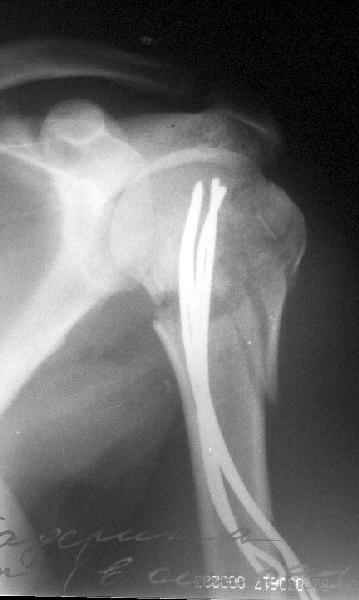

Да. У нас довольно скромный опыт такого остеосинтеза (по 2 случая - плечо и наружная лодыжка), дошли до использования самого простецкого троакара, через который мы сверлим кость и вводим 6 мм стержни, когда накладываем аппарат. Соответственно, в качестве забойника отлично работает любой стержень от аппарата Илизарова. Еще из наших туземных особенностей - страшная любовь к спицевым дистракторам, поэтому делали в нем. Результат у этой дамы неизвестен, т.к. она из области и уехала рожать сразу после остеосинтеза, сейчас прошло больше 5 месяцев...

Что-то, наверно, сделали мы не совсем оптимально, поскольку у Анатолия Федровича и его соратников как-то красивее "раскрываются" спицы в головке плеча - надеюсь, он прокомментирует и подскажет, что надо подправить.